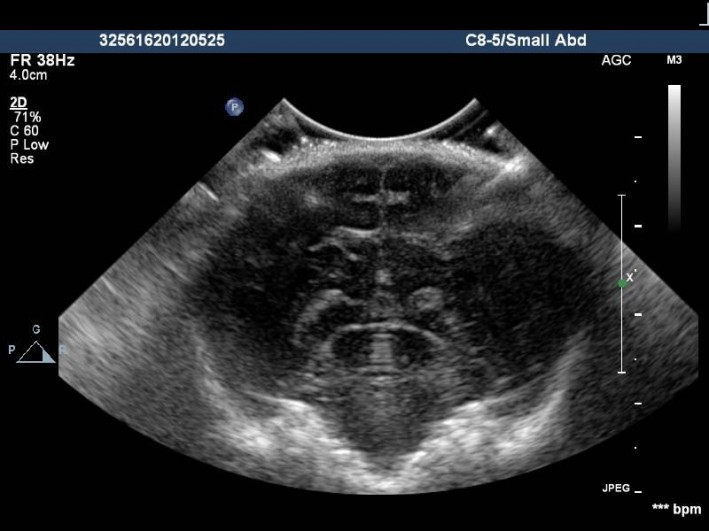

The only patient preparation is the clipping of hair overlying the area to be scanned because hair traps air and hinders the transmission of sound into the chest or abdomen.